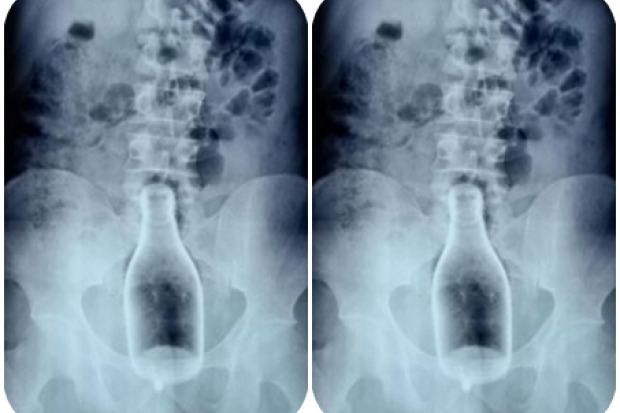

మందు బాబు చేసిన పనికి డాక్టర్లు షాక్ అయ్యారు. కాసేపు నోట మాట కూడా రాలేదు. అసలేం జరిగిందంటే తమిళనాడులోని నాగపట్టణం ప్రభుత్వాసుపత్రికి ఈ నెల 27న ఓ మందుబాబు వచ్చాడు. కడుపులో నొప్పిగా ఉందని డాక్టర్లకు చెప్పాడు. దీంతో అతనికి పరీక్షలు చేయించిన డాక్టర్లు.. అతని ఎక్స్ రే చూసి షాక్ కు గురయ్యారు. 250 మి.లీ. మందు బాటిల్ ఎక్స్ రేలో కనిపించింది. దీనిపై డాక్టర్లు ఆరా తీయగా అసలు విషయం బయటపడింది.

మద్యం మత్తులో బాటిల్ ను పురీషనాళంలోకి ఎక్కించుకోవడంతో.. అది నేరుగా పెద్దపేగులోకి వెళ్లిపోయింది. దీంతో అతను నరకయాతన అనుభవించాడు. ఇంట్లో ఎవరికీ చెప్పలేదు. చివరకు నొప్పిని భరించలేక ఆసుపత్రికి వచ్చాడు.

ఈ సందర్భంగా ఆసుపత్రి జనరల్ సర్జన్ పాండియరాజ్ మాట్లాడుతూ, ఎక్స్ రే చూసి షాకయ్యామని చెప్పారు. తన కెరీర్ లో ఇలాంటి కేసును ఎప్పుడూ చూడలేదని అన్నారు. పొరపాటున సీసా పగిలి ఉంటే అతని ప్రాణాలకే ముప్పు వాటిల్లి ఉండేదని చెప్పారు.